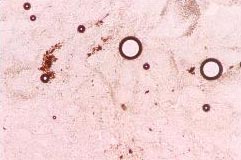

ไข่ของพยาธิ strongyloides spp. (ซ้าย) Trichuris spp. (ขวา)

พยาธิที่พบในเนื้อเยื่อบุลำไส้เล็ก